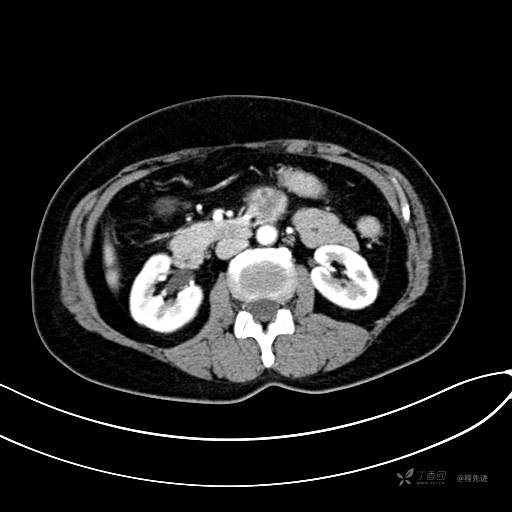

CT增强静脉期